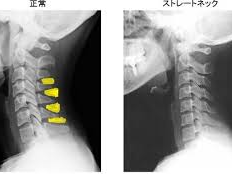

- 영상 검사: 엑스레이나 MRI를 통해 척추와 천장관절의 염증 및 손상을 확인합니다.